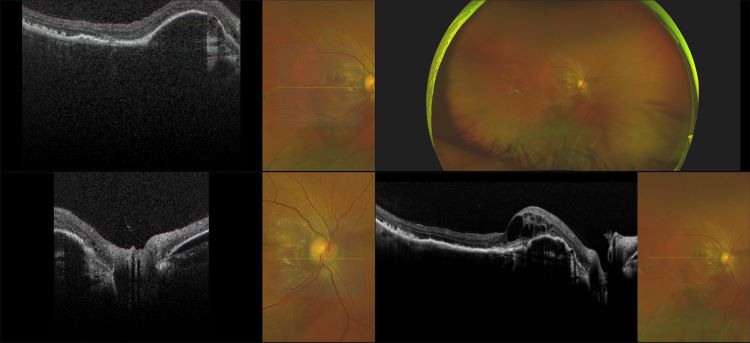

Monaco - Pigment Epithelial Detachment, RG, OCT